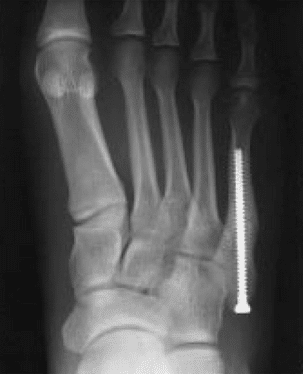

Treatment usually consists of immobilization in a cast. Patients are not usually allowed to place weight on the foot until the fracture heals. When the fracture does not heal, it is usually caused by a lack of blood supply to the bone. When this happens, surgery is warranted.

Surgery, usually reserved for competitive athletes like professional football players, involves making a small incision on the outside of the foot and placing a screw inside the bone, a plate, or wires. Sometimes, bone from another part of your body or cadaver is used to add structural support to the fixation and stimulate the healing process.

Most fractures take about 6-8 weeks to heal in a cast, splint or walking boot. If a bone graft is required, this may add additional 3-6 weeks. After this time period, rehab usually begins and can last an another 2-3 weeks. For athletes, this can be a season-ending injury.